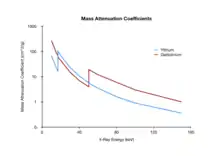

- Dual-energy imaging is based on exploiting the difference in the attenuation of tissue and bone - see Figure 7.16 - at different X- ray energies. It generally involves acquiring images at two X-ray energies and processing them to suppress either the bone or the tissue information. A simplified mathematical model, similar to that developed earlier earlier for DSA, assumes that monoenergetic radiation is used and no scattered radiation, once again, is detected, so that the transmitted radiation intensity through a region of bone and tissue, acquired at a low X-ray energy and following logarithmic transformation, can be given by: